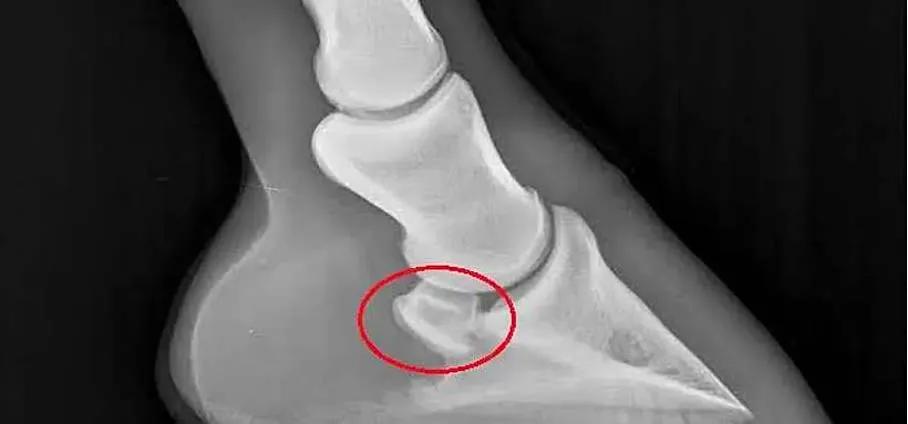

La vue latéro-médiale (figure 2) montre bien une inflexion du tendon fléchisseur profond du doigt lorsqu’il se trouve en rapport avec l’os naviculaire.

La tension physiologique du tendon et son changement de direction créent une pression du tendon sur l’os naviculaire.

En conséquence, lors du mouvement, le tendon fléchisseur profond doit pouvoir glisser sur la face tendineuse de l’os naviculaire, aussi appelée facies flexoria.

La facies flexoria, recouverte de fibrocartilage, et la bourse podotrochléaire, cette cavité synoviale entre l’os naviculaire et le tendon, sont essentielles pour assurer le glissement du tendon sur le scutum distal que représente l’os naviculaire.